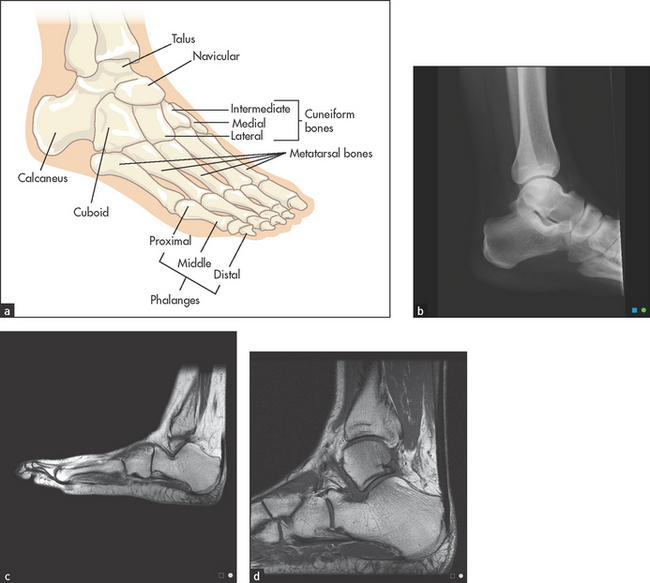

The ankle is a synovial hinge joint formed between the distal ends of the tibia and the fibula, and the talus bone (see Figure 24.38). Protrusions from the ends of the tibia and the fibula, which are called malleoli, form a socket that in combination with lateral ligaments stabilises the joint. The proximal part of the foot is called the tarsus and contains the seven tarsal bones (talus, calcaneus [heel], navicular, cuboid and the three cuneiform bones) with their supporting ligaments and joint capsules. The joints and ligaments around these bones allow the movements of the foot: inversion and eversion, dorsi- (upward) and plantar (downward) flexion.

Look at the skin. Note any swelling, scars, deformity or muscle wasting. Deformities affecting the forefoot include hallux valgus (fixed lateral deviation of the main axis of the big toe), clawing (fixed flexion deformity) and crowding of the toes, as occurs in rheumatoid arthritis. Sausage deformities of the toes occur with psoriatic arthropathy or Reiter’ss disease (see Figure 24.39).

Look for the nail changes that suggest psoriasis. Inspect the transverse arch of the foot, which runs underneath the metatarsophalangeal joints, and the longitudinal arch, which runs from the first metatarsophalangeal joint to the heel. These arches, which bear the weight of the body, may be flattened in arthritic conditions of the foot like rheumatoid arthritis. Calluses over the metatarsal heads on the plantar surface of the foot occur with subluxation of these joints (see Figure 24.40).